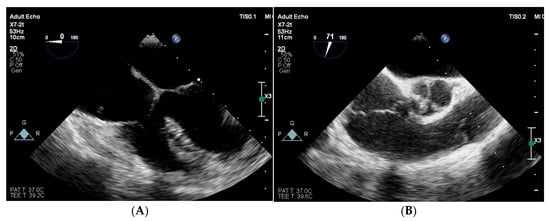

2. Case Presentation